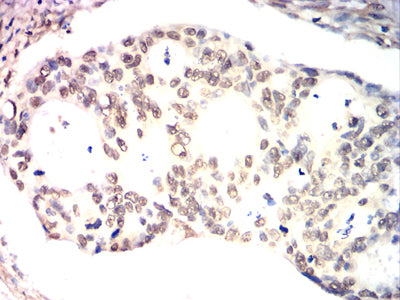

Immunohistochemical analysis of paraffin-embedded human ovarian cancer tissues using XRCC1 mouse mAb with DAB staining.